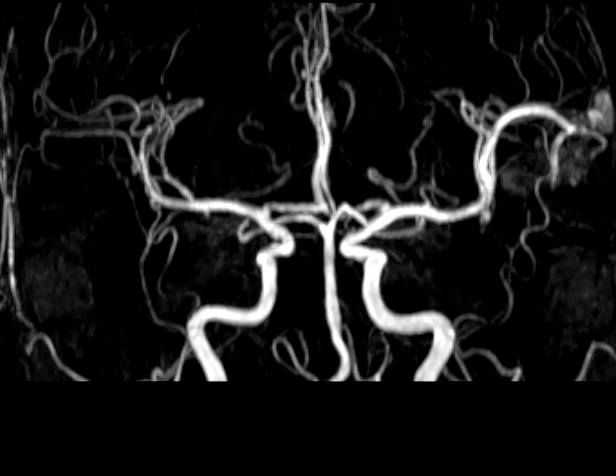

Khoa Chẩn đoán hình ảnh đã tiến hành chụp MRI sọ não với các xung MRA, MRV, dựng hình mạch máu não. Kết quả cho thấy, Bệnh nhân bị dị dạng mạch máu não (AVM) vùng thái dương bên trái có nguồn cung cấp máu từ động mạch não giữa cùng bên (bên trái), tĩnh mạch hồi lưu về xoang tĩnh mạch bên (bên trái).

Hình ảnh tổn thương

MRA